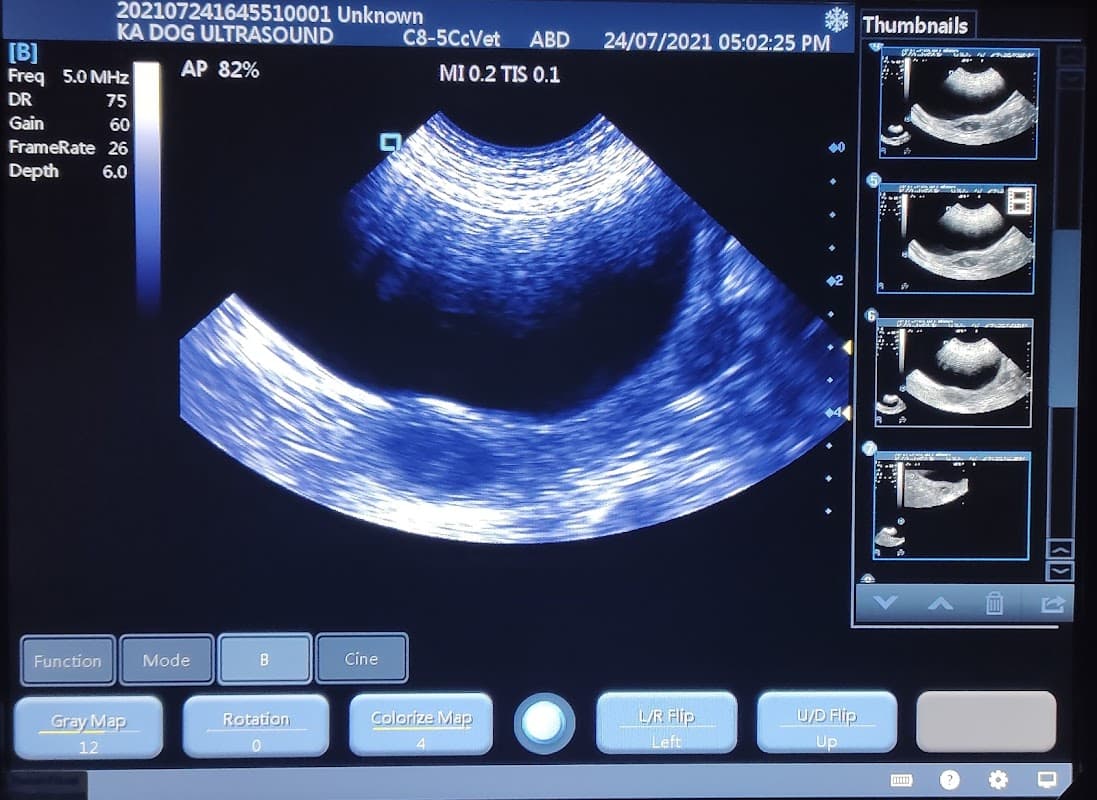

KA Dog Ultrasound Scanning Service

Offering highly-rated mobile dog ultrasound scanning services, KA Dog Ultrasound provides convenient and expert care directly to your home in Leeds.